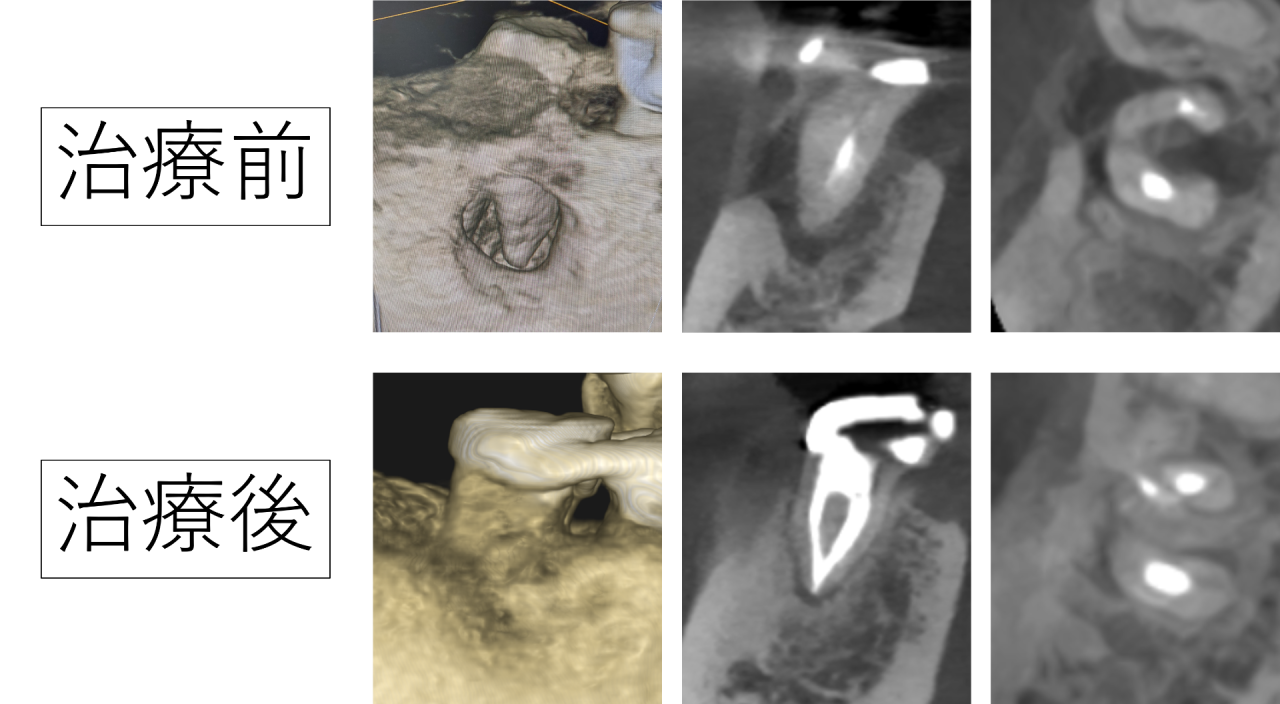

治療して3年後のレントゲンです。大きく溶けていた骨が再生し、ほとんど全て治っていました。大きく開いていた穴も、すべて塞がりました。